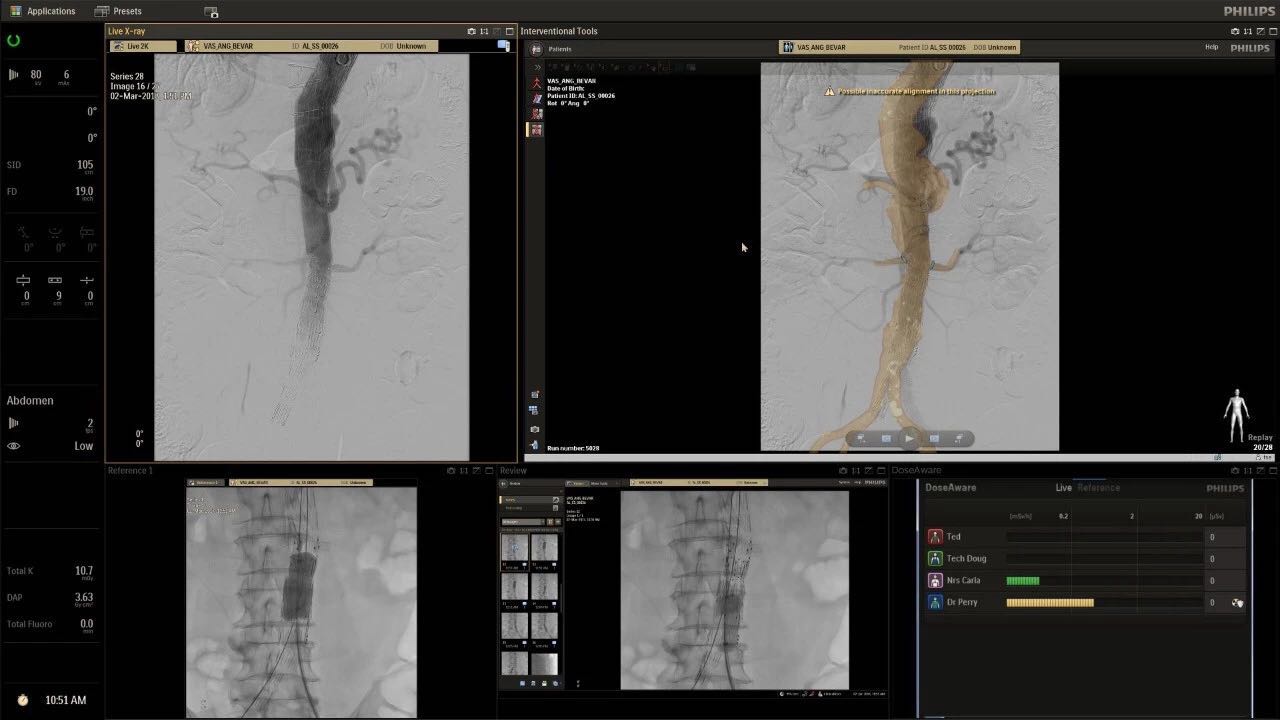

在日益復(fù)雜的干預(yù)期間,臨床醫(yī)生需要快速、輕松地可視化關(guān)鍵解剖結(jié)構(gòu)并確定手術(shù)過程中患者的變化。2019年1月17日,飛利浦宣布推出采用FlexArm的Azurion 7 C20,旨在提高圖像引導(dǎo)程序的定位靈活性。

帶有FlexArm的Azurion 7 C20 包含一系列創(chuàng)新技術(shù),使臨床醫(yī)生可以更輕松地在整個(gè)患者身上進(jìn)行二維和三維成像。當(dāng)臨床醫(yī)生移動系統(tǒng)時(shí),圖像光束自動保持與患者的對準(zhǔn),允許更一致的可視化并使他們能夠?qū)⒆⒁饬性谥委熒稀?/span>

(FlexArm C型臂可以沿著工作臺的兩側(cè)提供偏心成像。這允許醫(yī)生在左臂或右臂上進(jìn)行徑向進(jìn)入病例,完全或部分伸展,而無需移動患者或樞轉(zhuǎn)桌子。X射線束與手臂保持對齊,以促進(jìn)其整個(gè)長度的平滑導(dǎo)航,而無需進(jìn)行持續(xù)調(diào)整。)

飛利浦表示,采用FlexArm設(shè)計(jì)的Azurion 7 C20可提供卓越的靈活性和直觀的控制。該系統(tǒng)由智能運(yùn)動引擎驅(qū)動,可在八個(gè)不同的軸上移動,所有這些軸均由其單個(gè)“Axsys”控制器控制。臨床醫(yī)生的模擬測試表明,該系統(tǒng)有可能顯著減少患者,工作人員和設(shè)備的重新定位,從而改善微創(chuàng)手術(shù)的可及性,包括通過患者手腕進(jìn)入身體的手術(shù)(橈動脈入路),并降低患者的風(fēng)險(xiǎn)。無意中拔出電線和管子,以及節(jié)省大量時(shí)間。該系統(tǒng)非常適合混合手術(shù)室(OR),可滿足一個(gè)房間內(nèi)的多種專業(yè)需求,例如手術(shù)和血管內(nèi)手術(shù)的組合。

FlexArm在不少于8軸的情況下旋轉(zhuǎn),從而創(chuàng)建幾乎無限的靈活性來執(zhí)行成像,從頭部到腳部在左側(cè)和右側(cè)進(jìn)行2D和3D可視化。圖像光束保持與患者對齊,允許在旋轉(zhuǎn)或角度期間更好地可視化解剖結(jié)構(gòu)。使用Axsys運(yùn)動控制系統(tǒng)輕松操作支架。